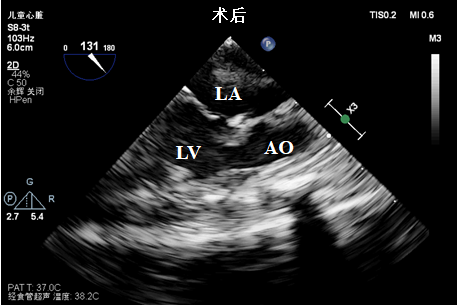

当晚9:30患儿进入手术室,开始进行手术。为了保证手术的顺利进行,术中行经食道超声监护,明确术前诊断及术后评估。术中所见与术前超声诊断一致,行“完全性大动脉转位调转术+冠状动脉移栽+动脉导管缝闭术”,术后经食道超声评估:心室与大动脉连接正常,各瓣膜未见异常,肺动脉与降主动脉间未见残余分流。经过心血管外科刘金平主任及其团队10个小时的手术,患儿顺利返回新生儿ICU。经过多学科的密切配合诊治,目前患儿恢复良好,生命体征平稳。

术中经食道超声(S8-3t探头)